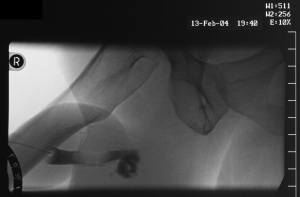

Schussverletzung